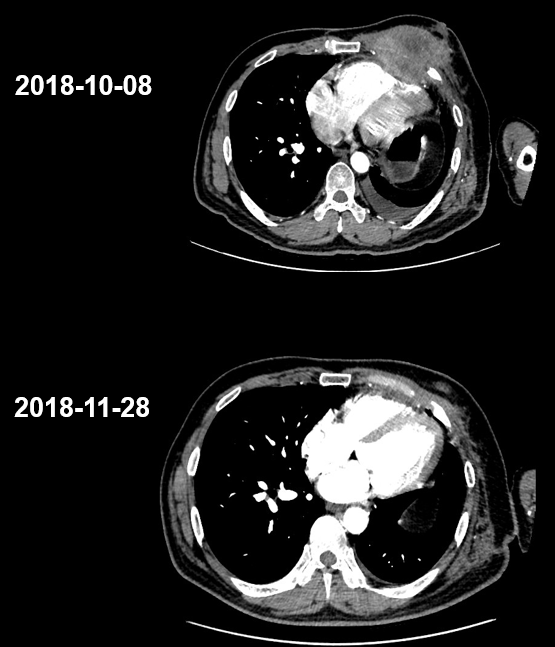

2018年10月,患者因“发现左胸壁肿物1月”再次就诊。门诊10月8日胸部CT示:1.左上肺肿物,大小约5.9*5.1*4.4cm,较前明显增大;2.左侧多根肋骨骨质破坏,周围见软组织影,考虑骨转移瘤(图5)。患者术后复发骨转移。

image009.png

图5.患者肿瘤复发转移

2018年10月16日起,患者接受信迪利单抗(200mg,d1)/安慰剂+吉西他滨(1650mg,d1,d8)+顺铂(122mg,d1)治疗4周期。用药2周期后,于2018年11月28日进行疗效评价为PR(图7)。期间患者出现Ⅱ度骨髓抑制,给予升白细胞等治疗后恢复。4周期治疗结束后,2019年1月12日再次进行疗效评价为PR(图8),治疗期间患者无明显不良反应。1月12日起,患者接受信迪利单抗(200mg,d1)/安慰剂维持治疗,共16周期,末次治疗时间为2020年2月3日,疗效PR(图9),PFS超过15个月,患者生活质量较前明显改善。维持治疗期间,患者每次输注临床用药后均有轻度的皮肤瘙痒症状,2-3天后缓解,考虑1级不良反应。

image013.png

图7.患者入组临床试验治疗2周期后疗效评价为PR